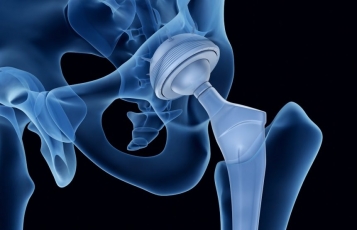

• Χειρουργικής Ισχίου, με έμφαση στην αρθροπλαστική